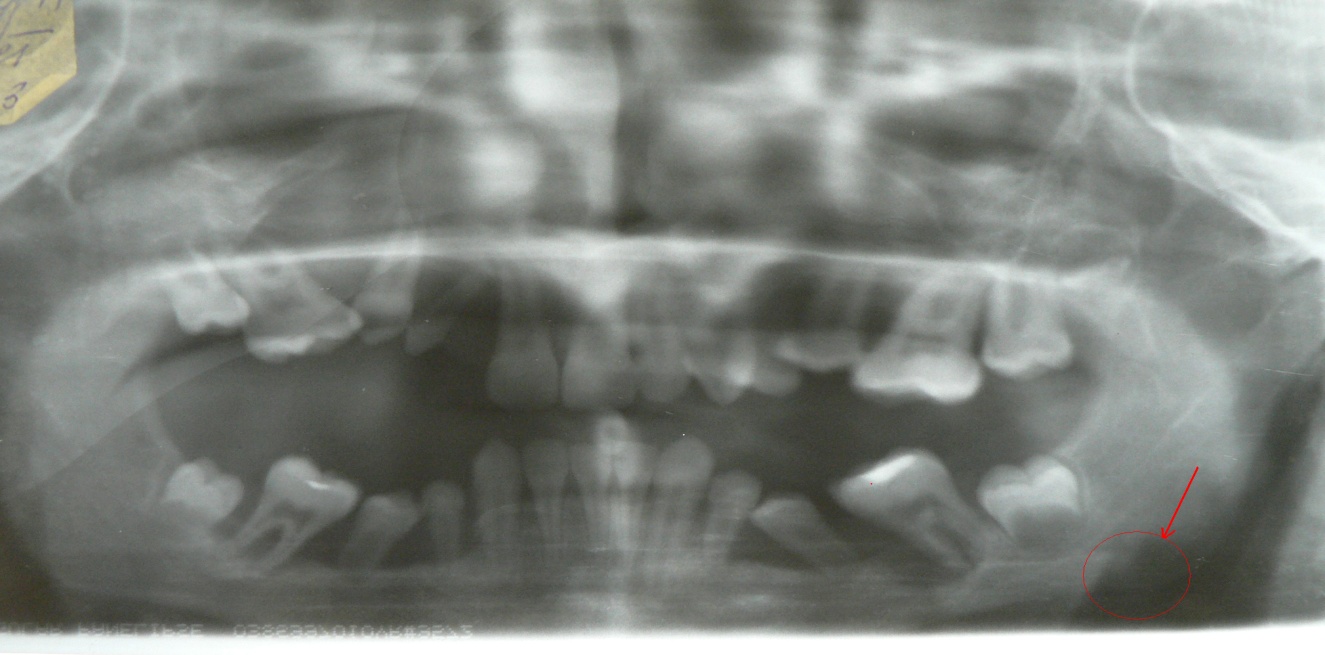

Данные ОПТГ: альвеолярный отросток нижней челюсти разрушен полностью от 33 до 43, на верхней челюсти в области 24, 25, 27 до ¾ длины корней. Вокруг медиального корня 37 обширный очаг деструкции кости округлой формы, захватывающий межкорневую перегородку; в области угла нижней челюсти слева – очаг деструкции размером 0,8 х 1,0 см со склерозированным передним контуром (рис.1.)

Рис. 1.